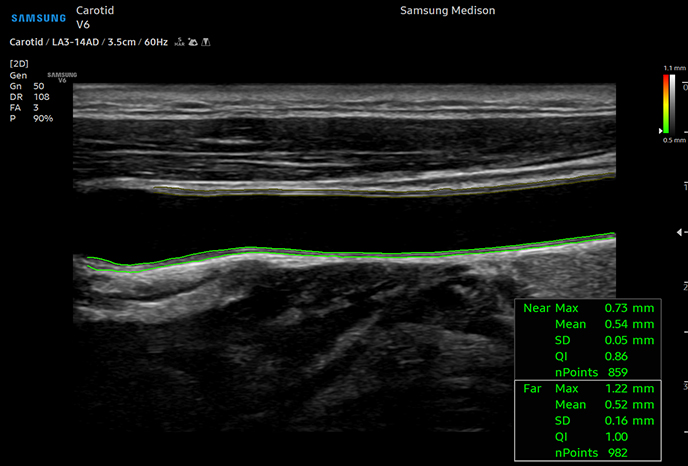

자동 IMT(경동맥 내막두께) 측정

동맥 분석